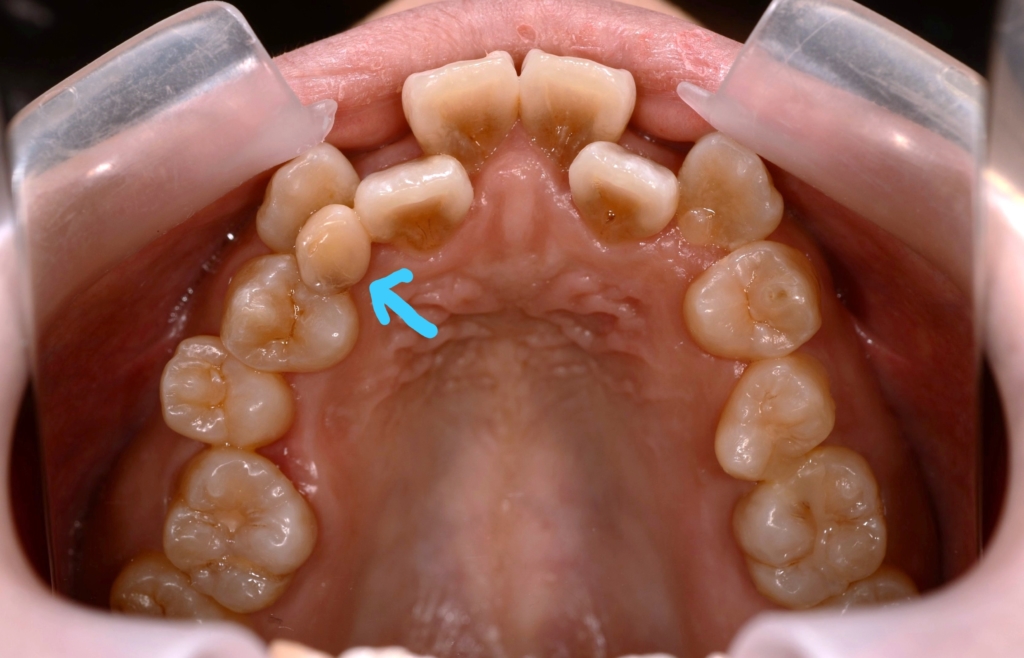

(青い線で囲まれた部分ですね)

レントゲン写真で確認すると、

この患者さんの場合、